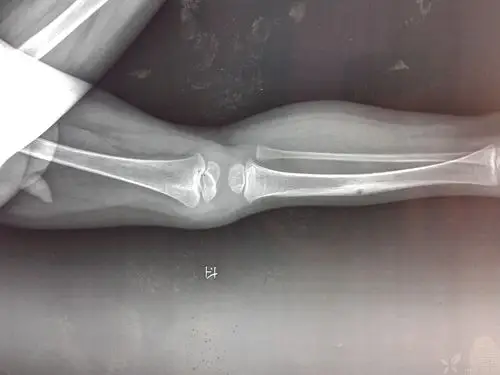

12岁儿童胫骨远端三平面骨骺骨折

写美篇患儿12岁,因车祸伤致右胫骨下段骨折伴骨骺损伤,右足皮肤挤挫伤

小儿胫骨远端干骺端骨折伴骨骺滑脱